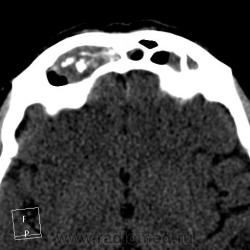

После пары менингитов на фоне синусита решили перебдеть. И вроде не зря... КТ: плотность содержимого в правой лобной пазухе 35-120 ед.Н. (мягкотканное с обызвествлением), в основной пазухе - 24 ед.Н (гнойной жидкости).

И пристеночный гайморит, и двусторонний этмоидит, и ринит, и односторонний сфеноидит, и фронтит, и очень тонкая костная пластинка между основанием передней черепной ямки и больной лобной пазухой - может быть реакция оболочек мозга...

По страшному снимку моему толком не видно, а вот на КТ множественные и разнообразные перегородки в пазухах видны хорошо. Я могу уверенно сказать только о следах жидкости в правой верхнечелюстной пазухе и субтотальном заполнении гомогенной жидкостью левой половины основной пазухи. Остальное, на мой взгляд, утолщение слизистой. Но на 100% утверждать не буду. В правой лобной я предполагаю (и только!) полипоз.

хр.фронтит: справа с образованием обызвествленных полипообразных образований,слева- в виде утолщения слизистой оболочки. Решетчатый лабиринт клиновидной кости занят патологическим содержимым жидкостной плотности(?) с обеих сторон. Основная пазуха: справа - пристеночное утолщение слизистой, слева - тотальное заполнение. Определяется утолщение слизистой верхнечелюстных пазух, видимо воспалительного характера.